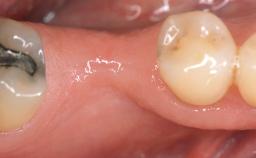

A 30-year-old woman was referred by her general dentist for evaluation of an esthetic complication related to previous implant treatment for congenitally missing maxillary lateral incisors. The patient’s chief complaint was the inadequate esthetic appearance of her smile. The case demonstrates the use of a combined approach to achieve optimal results. Two different flap designs - a tunnel technique and a coronally advanced flap - are employed based on the surgical objectives for the affected site.

# of Teeth 2

# of Implants 2